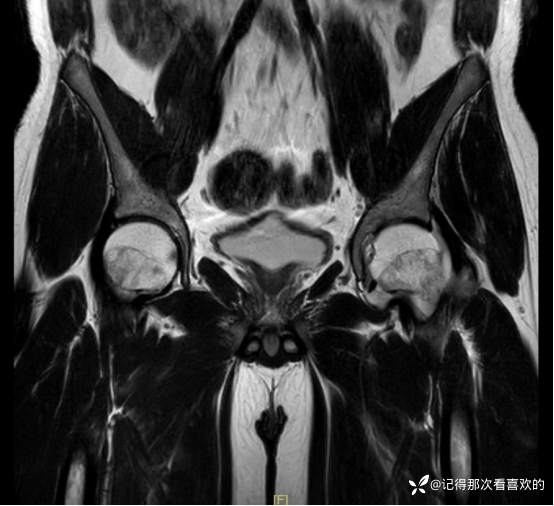

06-05 骶髂关节MRI平扫:1、双侧骶髂关节改变,符合为强直性脊柱炎所致。请结合临床实验室检查结果。2、左髋关节少量积液。请结合临床及其他检查,随诊。